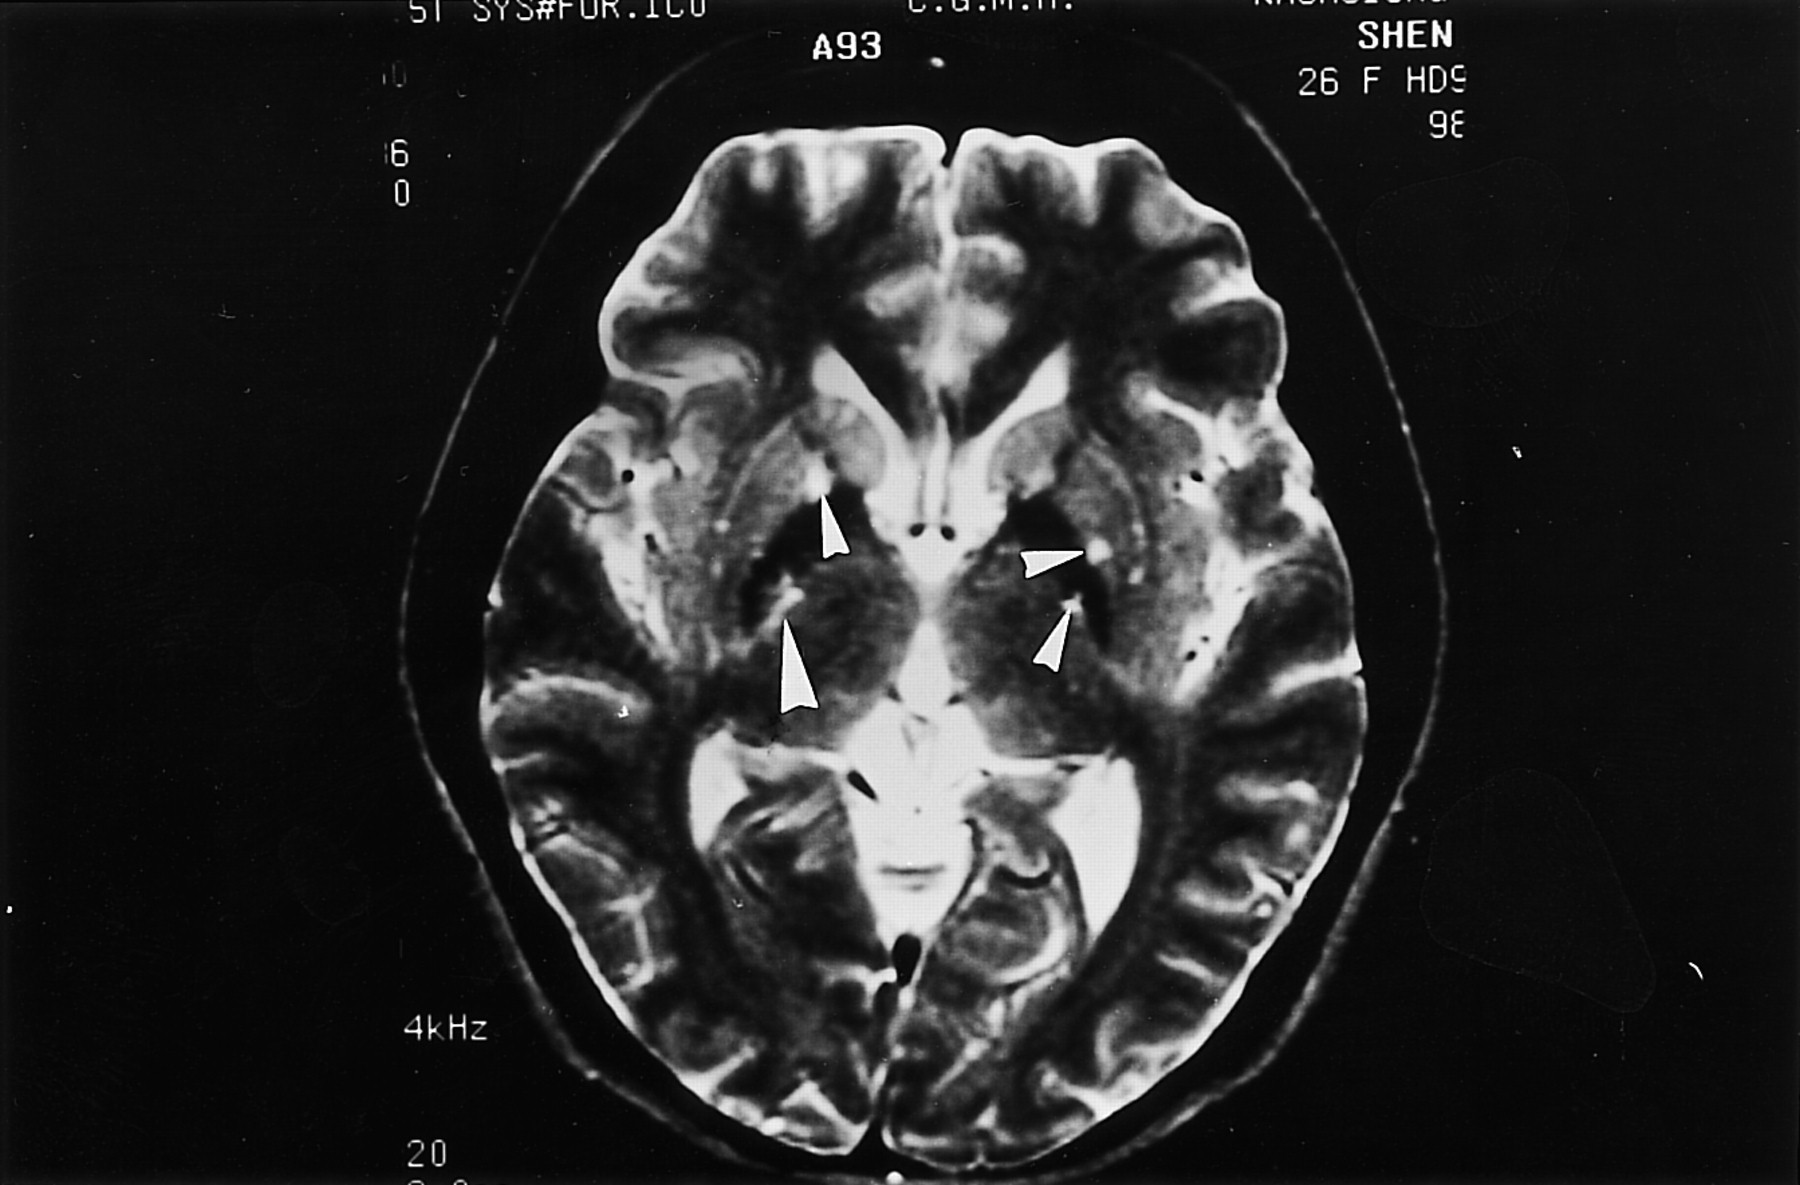

Οι μελέτες απεικόνισης, όπως η αξονική ή η μαγνητική τομογραφία μπορεί να δείξουν κάποια χαρακτηριστικά που υποδηλώνουν φυματίωση των μηνίγγων.